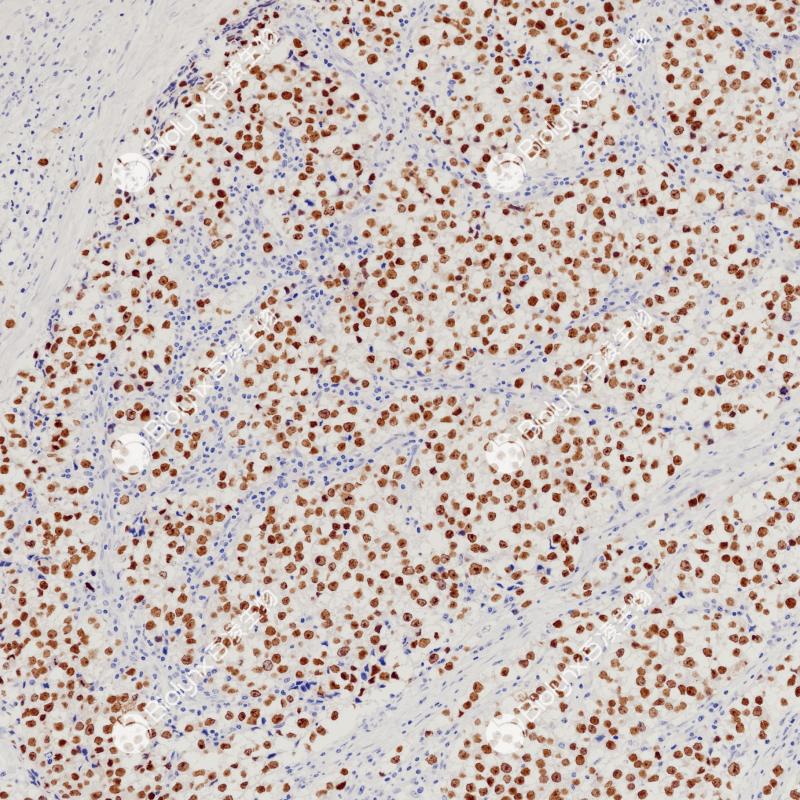

SALL基因家族成员编码锌指转录因子,在发育过程中高度表达。Sall-like蛋白4 (SALL4)是胚胎多能性的主要调节因子,并参与干细胞活动相关的过程。正常睾丸的精原细胞中也有SALL4的表达。SALL4在生殖细胞中的表达使其成为生殖细胞肿瘤如精原细胞瘤、胚胎癌、卵黄囊瘤和畸胎瘤的有用标记物。

阳性对照

精原细胞瘤

亚细胞定位

细胞核